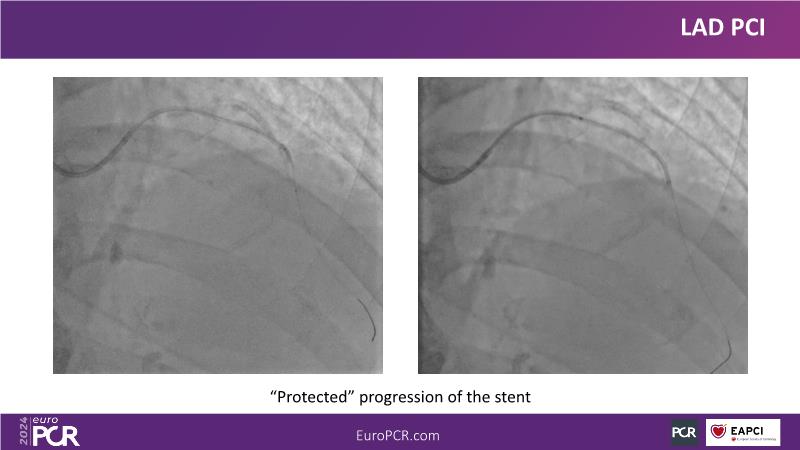

Explore this session to uncover the common association between calcium and acute coronary syndrome, and how intravascular lithotripsy (IVL) offers a safe solution for calcified lesions, with comparable procedural success rates. However, note that ACS cases involving calcium may lead to higher major adverse cardiac events (MACE). Special attention is warranted for women due to their propensity for adverse outcomes. Discover how the C2 + IVL catheter enhances procedural flexibility, yet high intracoronary imaging rates did not yield differences in MACE. Additionally, learn about the potential role of IVL in treating in-stent restenosis (ISR).

- To share clinical experience to uncover practical tips and techniques for intravascular lithotripsy in complex calcified lesions